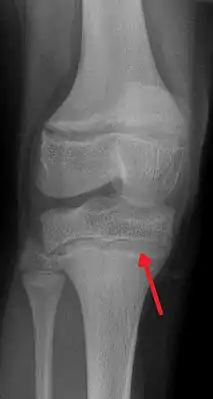

![]() Рентгенография. Характерное изменение метафиза при отравлении свинцом. | |